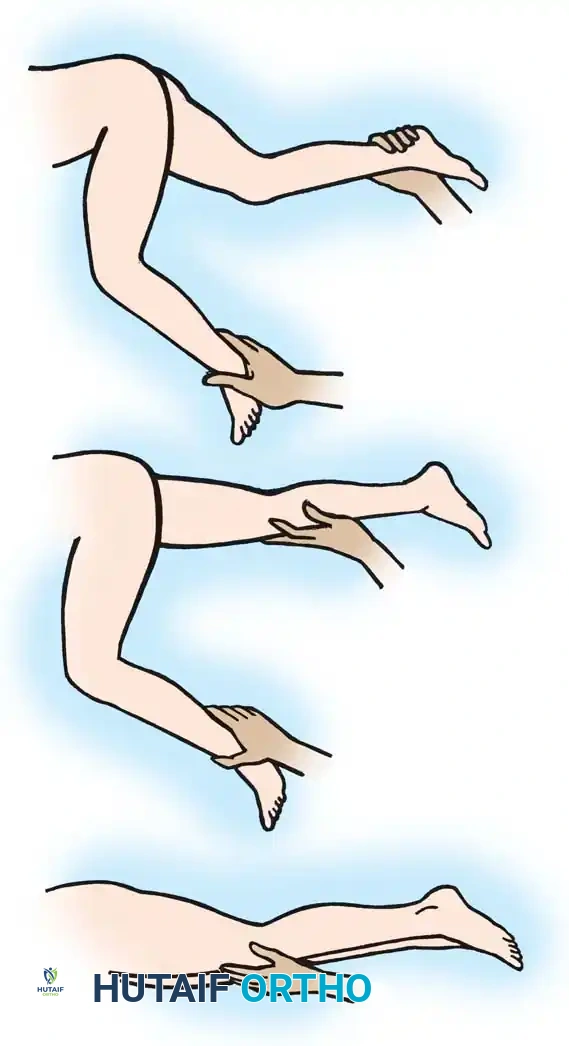

Hamstring strength, spasticity, and knee contractures are assessed with the patient in both prone and supine positions.

Prone Assessment: The examiner extends the hips maximally and exerts gentle downward pressure on the calves. The angle formed between the femur and the tibia after dynamic spasticity has been overcome represents the true degree of fixed soft-tissue contracture behind the knee.

Supine Assessment (Popliteal Angle): The examiner stabilizes the contralateral knee in maximum extension. The ipsilateral hip is flexed to 90 degrees, and the knee is passively extended. If knee extension is limited, hamstring tightness is present.

Fig. 30-20 Testing for hamstring spasticity and contracture. A, Patient is supine with hips extended. Pressure is exerted over knees, forcing them into extension. Flexion remaining in knees is absolute knee flexion contracture. B, Knee on side to be tested is flexed, while opposite knee is stabilized in extension. C, Attempted flexion of hip results in more flexion of knee.